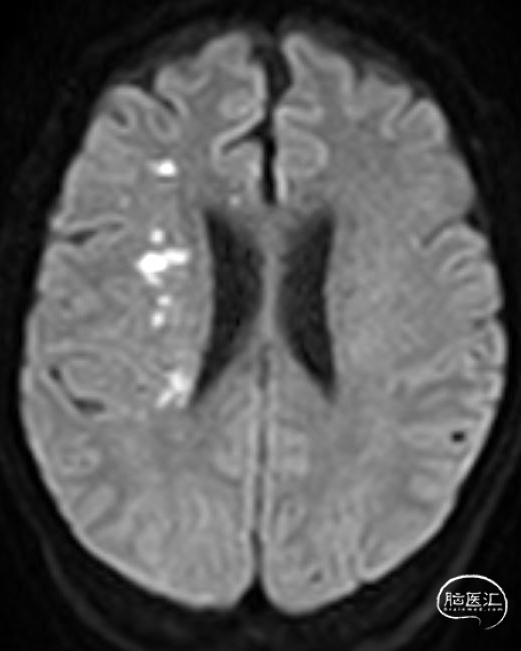

02、术前影像

为进一步评估梗死大小和颅内情况,磁共振显示颈内动脉闭塞,小的核心梗死。